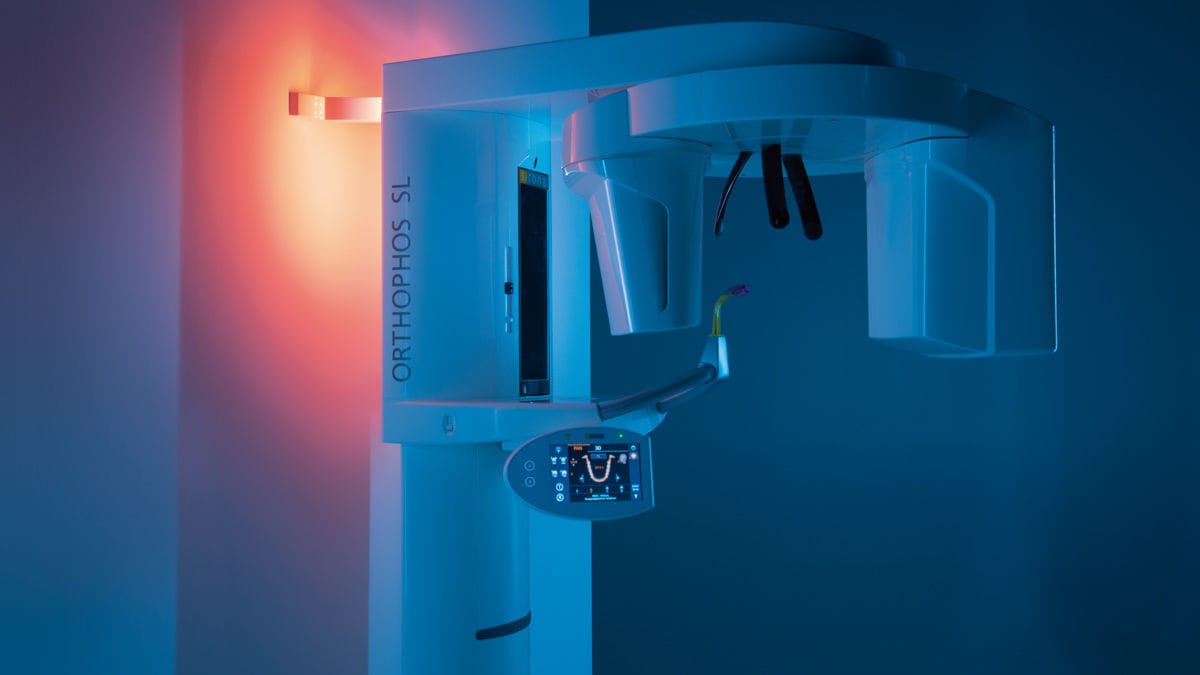

Diş hekimliğinin uzmanlık alanlarından birisi olan “Ağız, Diş ve Çene Radyolojisi” anabilim dalının işlevi; hastalıklara doğru tanı koymak ve doğru tedavi planı yapmaktır. Oral Diagnoz ve Radyoloji; ağız, diş veya çevre doku şikayetleriyle diş hekimine başvuran hastaların, ilk karşılaştıkları uzmanlık alanıdır. Hastayla tanışmakla başlayıp, tedavi planlamasıyla sona eren süreci doğru bilgilerle yönetmek, öncelikle hastaların çoğunluğunda bulunan “diş hekimi” fobisini “her anlamda!” yıkmak ve güvenini kazanmak adına önemlidir. Hastaların geçmiş ve var olan hikayesinde yer alan, tıpla ilgili sorunlarının belirlenmesi, ayrıntılı ağız içi ve ağız dışı muayenenin yapılması, periapikal-panoramik-tomografik röntgen bulgularının doğru yorumlanması, hastalıklarının ayırıcı tanılarının doğru konulması ve tüm bu verilerin ışığında doğru tedavi planının yapılması bu anabilim dalının uzmanlığıdır. ORTHOPHOS SL 2D Sharp Layer Teknolojisi(SL) sayesinde yüksek çözünürlükte panoramik görüntüler sadece keskin katmanda elde edilmekle kalmayıp, ayrıca özel vakalarda görüntü içinde (lingual/bukkal) düzlemde analiz edilmesini sağlar. 5cm x 5cm hacminde başlayan ve üst solunum yolu analizi için 11cm x 10cm kadar çıkan görüş alanına sahip olan görüntüleme cihazıdır. ORTHOPHOS SL 2D,DCS(Direct Conversion Sensor) sensör ve SL teknolojisi ile panoramik görüntüleme konusunda büyük talepleri olan dişhekimlerini bile tatmin eden görüntü sunmaktadır. 3 noktalı kafa sabitlemesi ile stabil konumlandırması, dengeli kolları ve patentli oklüzal ısırma çubuğu ile her görüntüdeki eşsiz çözünürlüğü garanti etmektedir. Öncü SIDEXIS 4 yazılımı ile birlikte klinik iş akışı için yenilikçi çözümlerin benzersiz çeşitliliğini sunmaktadır. Hastanemizde kullandığımız ORTHOPHOS SL cihazımızda mükemmel uyum sağlayan,hoş atmosfer için 30’dan fazla renk seçeneği ile rahatlatıcı ambiyans aydınlatması hastaların kapalı alan fobisi için ayrı bir özelliğide sahip olduğundan hastalarımızın daha rahat,sorunsuz ve hızlı görüntü alabilmemizi sağlıyor. Genellikle hastanemize gelen hastalarımızın birçoğu diş röntgenlerinden alacağı radyasyon miktarından dolayı röntgen bölümlerine isteksiz geliyorlar. Fakat dışarıdaki herhangi bir hastane kurumlarında ya da kliniklerde kullanılan röntgen cihazları ile hastanemizde kendi kullandığımız ORTHOPHOS SL cihazı arasındaki farklar şunlardır; Aşağıdaki tabloda okuduğunuz bilgilerde radyasyon miktarları kullandığımız ORTHOPHOS SL cihazın verdiği radyasyon ile karşılaştırılmıştır. Bunun sonucunda her cihazın aynı radyasyon dozu vermediği,kullanılan cihazların alınan radyasyon değerini değiştirdiğinin sonucuna varıyoruz. Düşük Doz: 2D Görüntü Dozlama aralığında CBCT 3D GÖRÜNTÜLEME *Endodonti hekimlerin vazgeçilmez görüntüleme cihazı periapikal röntgen cihazları, kanal tedavilerinde, kök uçlarında belirlemeyen lezyon vb gibi durumlarda diş ve diş çevrelerinde oluşan vakaları daha yakından görmeyi kolaylaştıran röntgen cihazlardır. Aynı zamanda bir kablo sınırları olmadan, opsiyonel WiFi *Tek tuş hızlı çekimi ile hastanın film görüntüsü hızlıca ekrana düşme özelliğine sahiptir.